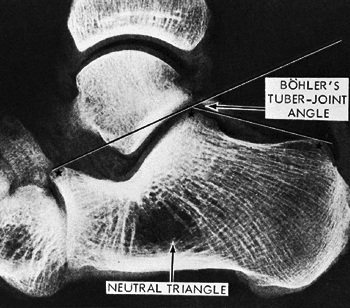

The Böhler tuber joint angle: This is

represented by the supplement (180 degree measured angle) of two lines:

a line from the highest point of the anterior process of the calcaneus

to the highest point of the posterior articular surface and a line

drawn between the same point on the posterior articular surface and the

most superior point of the tuberosity. Normally, this angle is between

25 and 40 degrees; flattening of this angle indicates collapse of the

posterior facet (Fig. 52.2).

Comparison views of the contralateral foot may help detect subtle changes in the Böhler angle.![]() Figure Figure

52.2. The landmarks for measuring the Böhler angle are the anterior and

posterior facets of the calcaneus and the superior border of the

tuberosity. The neutral triangle, largely occupied by blood vessels,

offers few supporting trabeculae directly beneath the lateral process

of the talus.(From Harty MJ. Anatomic considerations in injuries of the calcaneus. Orthop Clin North Am 1973;4:180.)